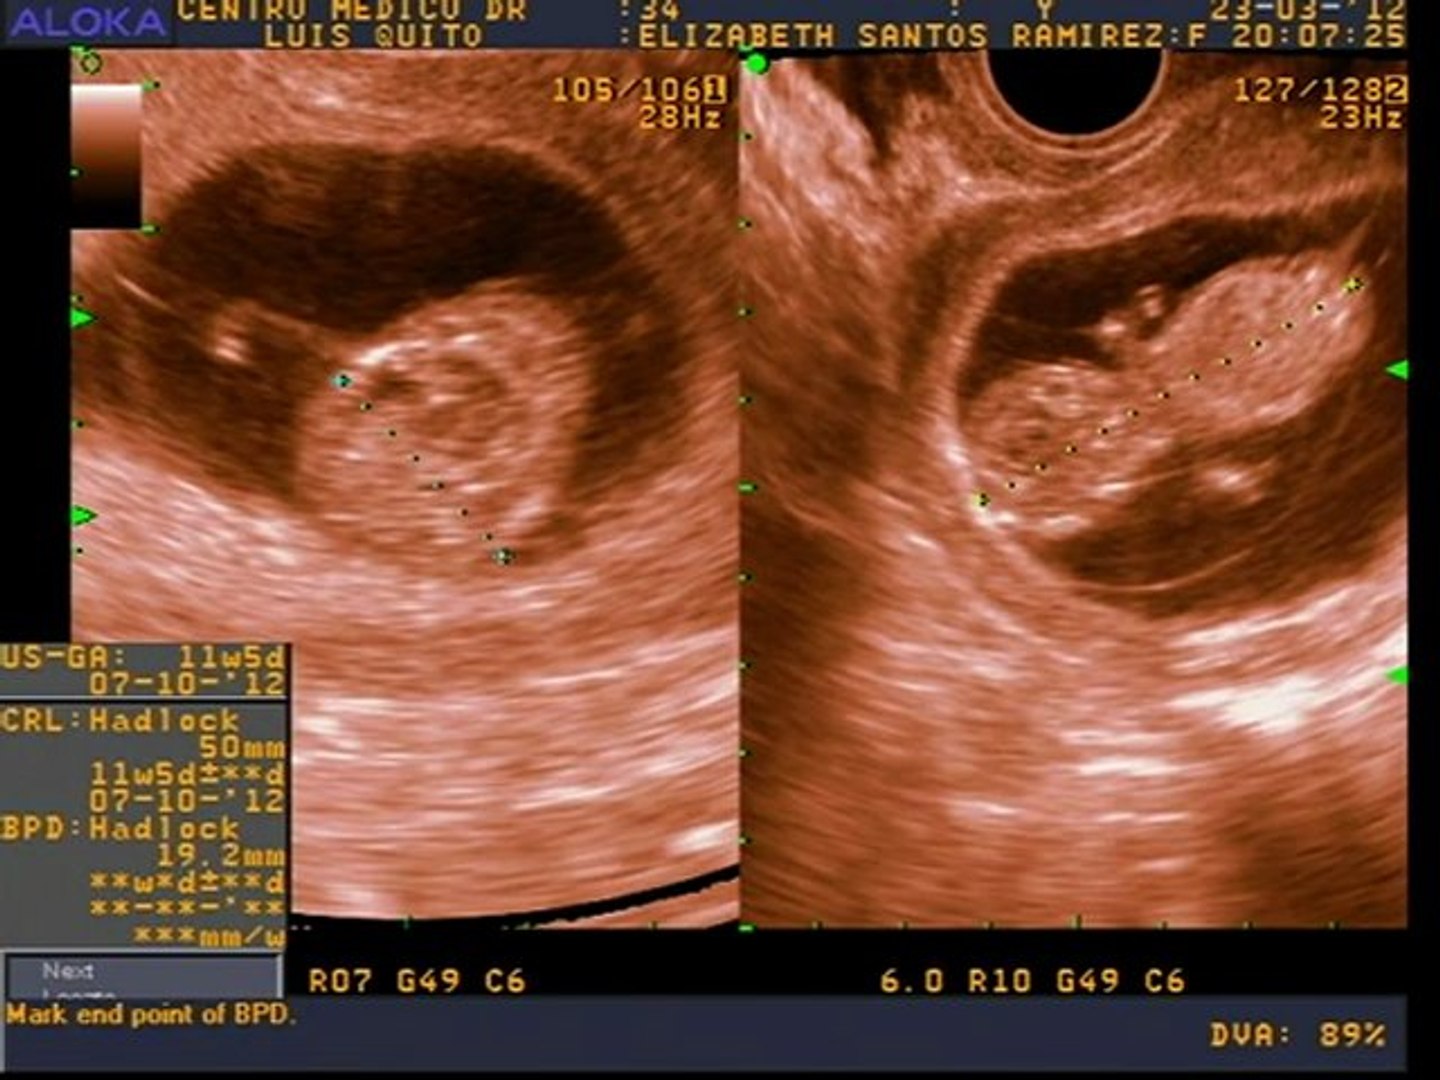

A partir de la semana 11 cuando el feto mide entre 45 y 84 milímetros ya se realiza la ecografía de cribado de alteraciones cromosómicas y de alteraciones anatómicas mayores. Con apenas 12 semanas de embarazo este bebé ya cuenta con todas las estructuras corporales básicas que podrán verse en el momento del nacimientoEs un ser humano completo que podemos contemplar en ecografía 4DLo que le falta es tiempo de maduración para que todos sus órganos logren completar su desarrollo y la proporcionalidad entre la cabeza y las. En la semana 11 de gestación el feto mide alrededor de 4 cm desde la cabeza al coxis.

La cabeza representa la mitad de su longitud como se aprecia en esta silueta de perfil de una ecografía en 2D. Tu cuerpo en la semana 11 de embarazo gemelar. Te explicamos cómo evoluciona tu cuerpo a las 11 semanas de embarazo y cómo va creciendo tu bebé.

Ecografía en 2D y 3D de embarazo de 111 semanas. En la semana 11 de embarazo tu bebé comenzará a formar sus órganos sexuales.